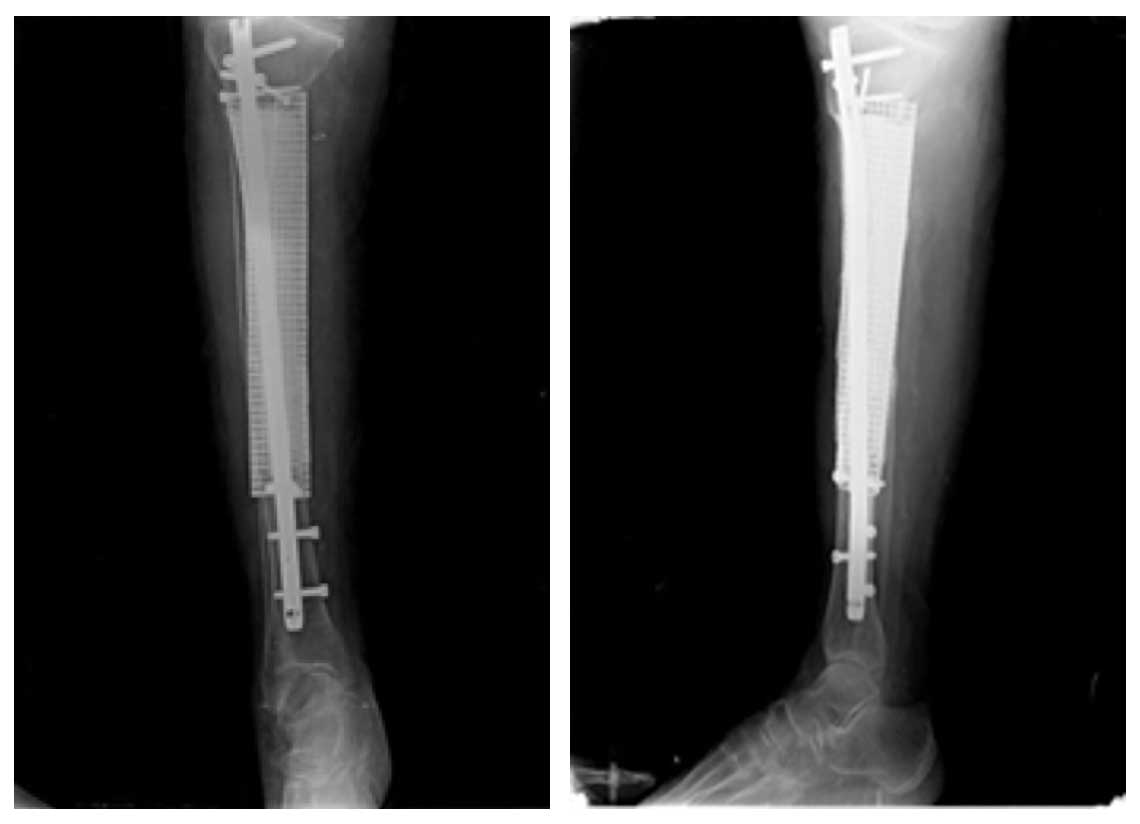

Ameliyat Sonrası: Röntgende kemiğin tümörlü kısmının çıkarıldığı oluşan boşluğun titanyum mesh ve kemik çimentosu ile doldurulması ve titanyum çivi uygulanımı görülmekte.